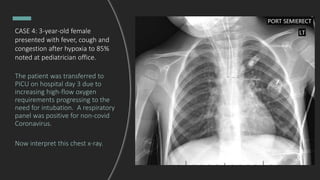

CASE 4: 3-year-old female

presenting with fever, cough and

congestion after hypoxia to 85%

noted at the pediatrician’s office.

Interpret this chest x-ray

CASE 4: 3-year-old female presenting

with fever, cough and congestion

after hypoxia to 85% was noted at

the pediatrician’s office.

Bilateral perihilar interstitial and

peribronchial thickening, representing

edema versus a worsening viral

process versus reactive airway

disease.

presented with fever, cough and

noted at pediatrician office.

The patient was transferred to

PICU on hospital day 3 due to

increasing high-flow oxygen

requirements progressing to the

need for intubation. A respiratory

panel was positive for non-covid

Coronavirus.

Now interpret this chest x-ray.